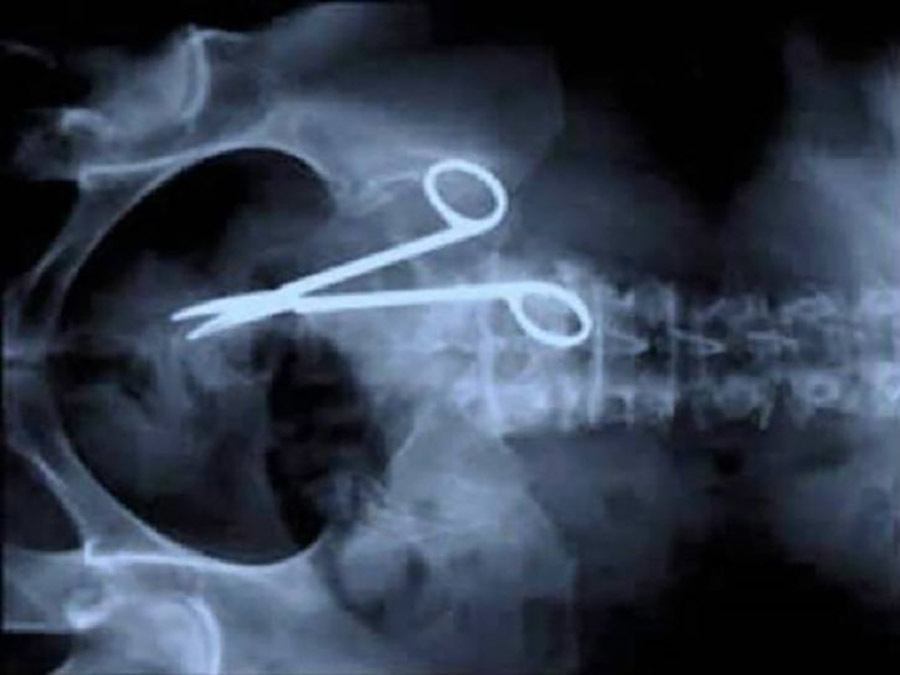

A man was stabbed in the head with scissors during a bar fight. He recovered.

This pair of nine-by-four cm scissors slid down this man’s esophagus when he tried to use them as a toothpick.

Sometimes the surgeons don’t remember all of their instruments.